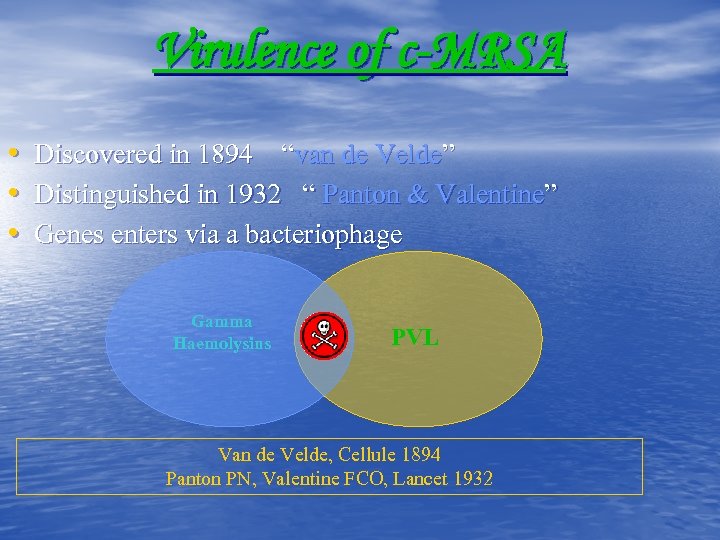

Virulence of c-MRSA • • • Discovered in 1894 “van de Velde” Distinguished in 1932 “ Panton & Valentine” Genes enters via a bacteriophage Gamma Haemolysins PVL Van de Velde, Cellule 1894 Panton PN, Valentine FCO, Lancet 1932

Virulence of c-MRSA • • • Discovered in 1894 “van de Velde” Distinguished in 1932 “ Panton & Valentine” Genes enters via a bacteriophage Gamma Haemolysins PVL Van de Velde, Cellule 1894 Panton PN, Valentine FCO, Lancet 1932